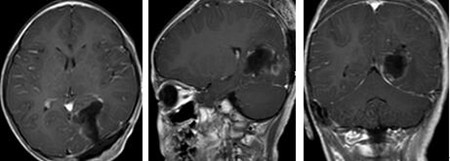

▲术后

为晓霖完善术前检查,小儿神经外科及其团队在全麻下行为晓霖进行“左侧顶枕开颅左枕占位性病变切除术”,术中晓霖的大脑大静脉被保护完好,切除的肿瘤大小约4×4×4cm,术后患儿好转。

术后病理:左枕叶间变性室管膜瘤 WHO III级。